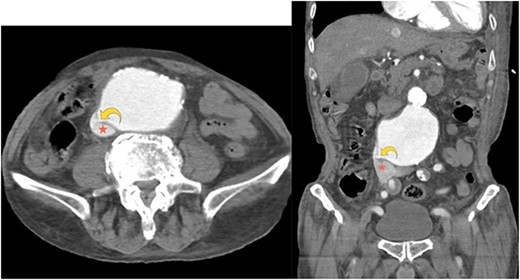

A right-upper quadrant abdominal ultrasound demonstrated an AAA, measuring 5.5 cm × 8.5 cm. Computed tomography angiography of the abdomen and pelvis showed a 9.2 cm aneurysm of the infrarenal abdominal aorta compressing the IVC (Fig. 1a). Furthermore, an aortocaval fistula was noted (Fig. 1a and b). There was no evidence of an aortic rupture or dissection. Of note, the dimensions and anatomy of AAA were amenable to endovascular repair.

Axial computed tomography angiography image showing a small focal defect in the aortic wall (curved yellow arrow). Abnormal early opacification of the IVC (red star) can be noticed in this arterial phase study. These findings are consistent with an aortocaval fistula. No retroperitoneal hematoma is observed.

Aortocaval fistulas are best identified on multidetector computed tomography angiography. Presence of contrast in both the aorta and IVC (on arterial phase images), which was seen in our patient, is pathognomonic for arteriovenous fistula. However, in case of compression of IVC from an AAA and no obvious fistulous tract, presence of contrast in iliac or renal veins on arterial phase and loss of aortocaval fat plane may be indicative of an aortocaval fistula [12].